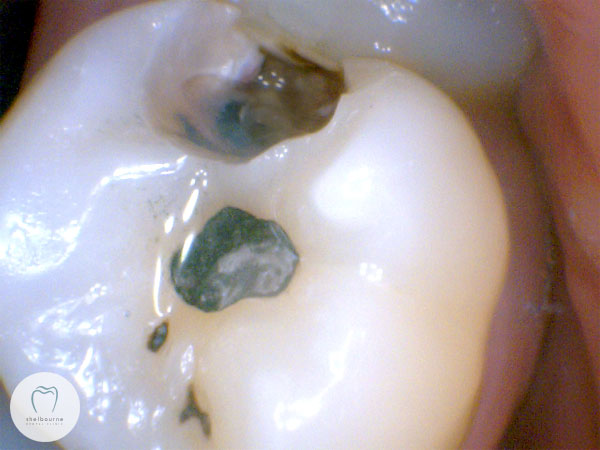

The patient, who I was seeing for the first time, reported significant pain from the upper left teeth. Nothing was obviously visible, no teeth were tender to pressure or biting. Here’s a photo of the area. Two small fillings in this tooth, but it looks fine.

So having found the damage, and numbed the tooth to ensure it’s not sensitive to the water spray, I polished out the existing filling and a small portion of tooth. You can quite clearly see the decayed area now. Unfortunately this decayed area just kept going, and the outlook for this tooth isn’t great.